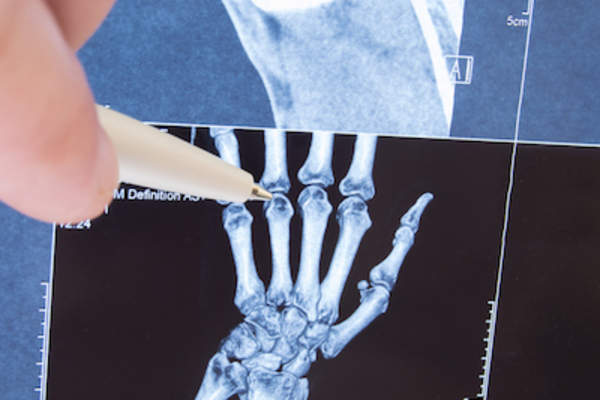

周围性关节炎和小关节炎

强直性脊柱炎本质上是轴性的,这意味着它主要影响身体的轴或中心。强直性脊柱炎患者也可以外周疾病活动或影响身体外部的关节炎,如肘部、手、手腕、手指、膝盖、脚踝、脚和脚趾。目前很少有研究探讨治疗强直性脊柱炎外周活动的有效方法,但是常用消炎药和缓效抗风湿药治疗.